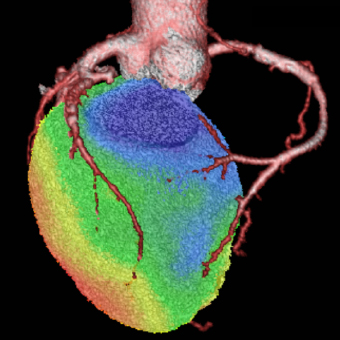

a. 心臓CT

SPECT/CT融合画像

図3 労作性狭心症症例。後側壁〜後下壁の心筋虚血はLCXおよびRCA両方の有意狭窄による。